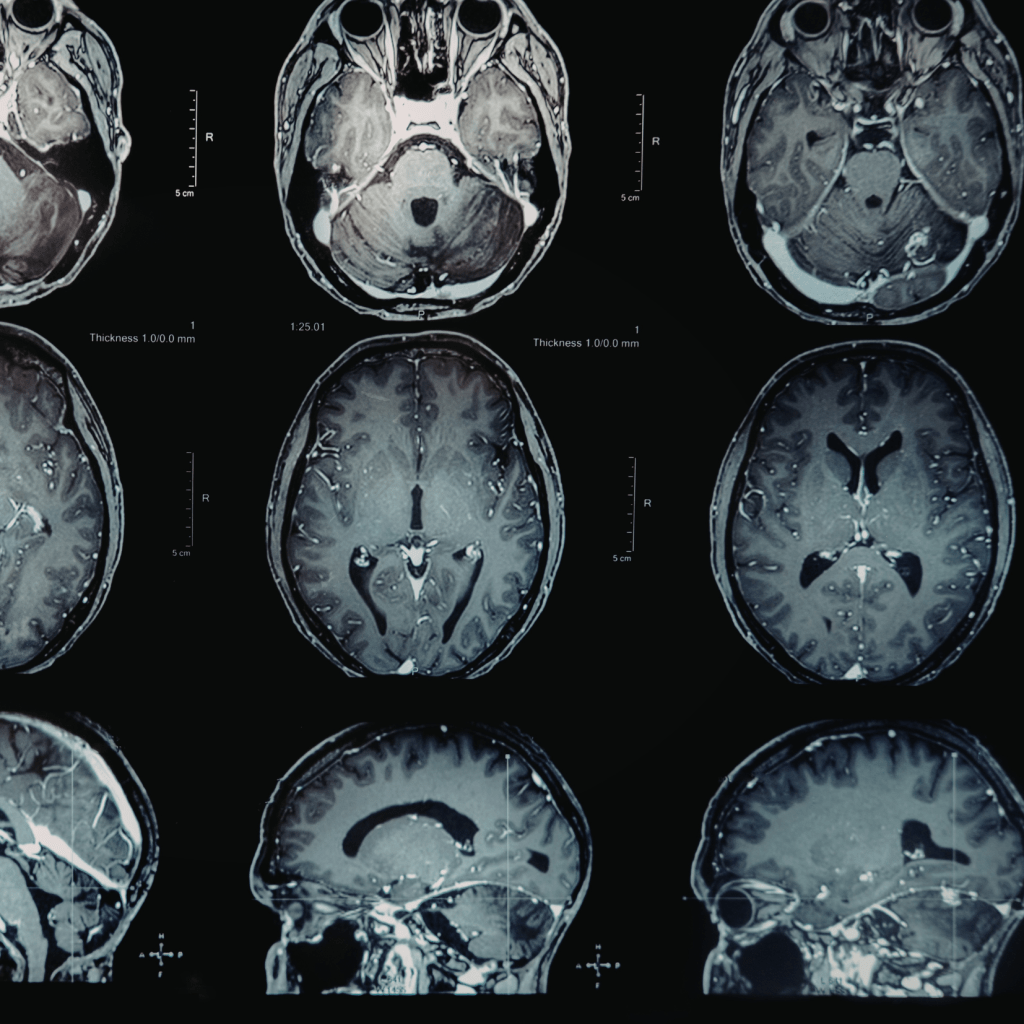

Chiari malformation is basically when part of your brain decides it’s tired of the whole “staying inside the skull” expectation and starts slipping downward into the spinal canal. Doctors describe it as a structural abnormality; Della would describe it as your cerebellum trying to Irish‑exit your cranium.

- Type I: The “surprise!” version. Often shows up in adulthood, sometimes after an MRI you got for something completely unrelated, like checking if your sinuses are haunted.